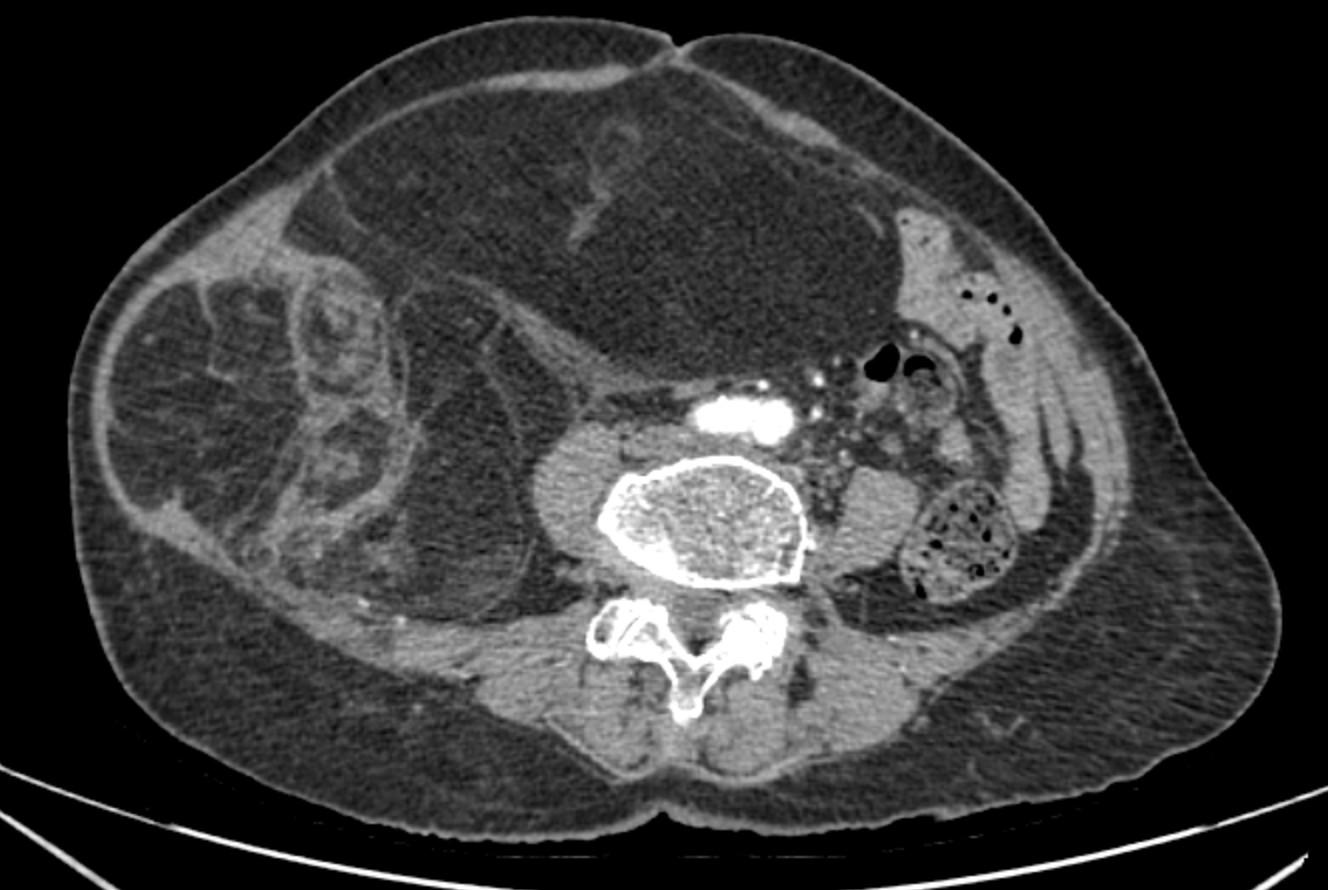

Phim chụp CT ổ bụng của bệnh nhân.

Chẩn đoán hình ảnh (CT ổ bụng có thuốc cản quang) cho thấy khối choán chỗ sau phúc mạc, kích thước 28 × 15 cm, cấu trúc hỗn hợp tổ chức mỡ – đặc , đè đẩy tạng trong ổ bụng nhưng không có dấu hiệu xâm lấn các tạng lân cận. Kết hợp lâm sàng và hình ảnh học, bệnh nhân được chẩn đoán sarcoma mỡ sau phúc mạc.